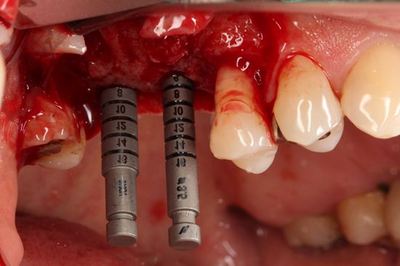

深度ゲージで確認します。

![]()

スタンダードプラスインプラントΦ4.1とΦ4.8 長さは同じ8mmです。

無事埋入を終えました。